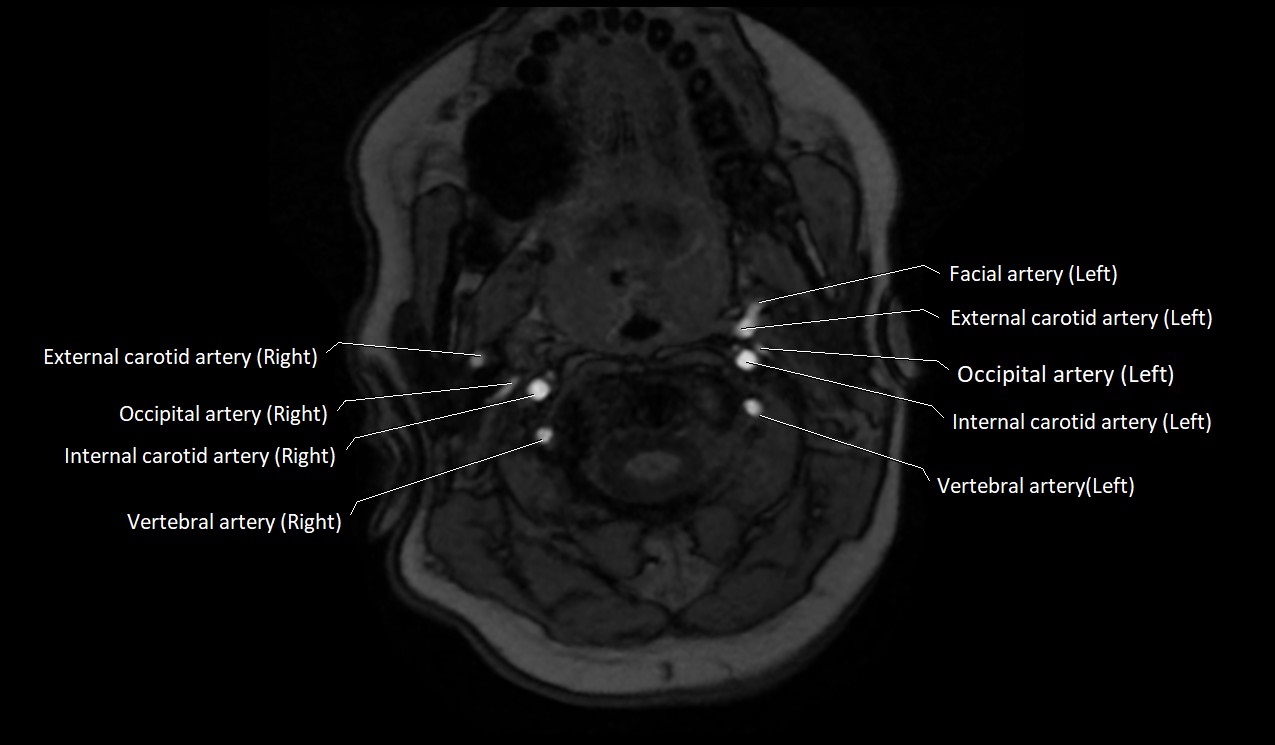

CT image

image